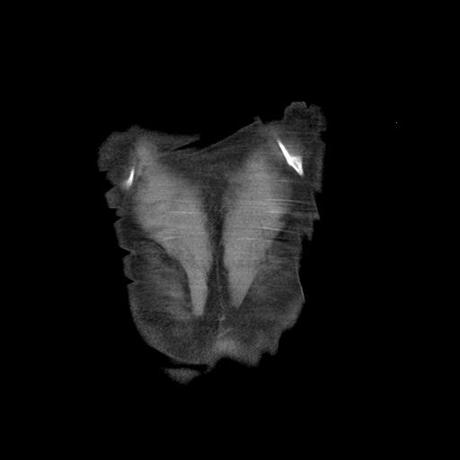

Se realiza volumen de tórax en fase simple, desde los opérculos torácicos hasta los hemidiafragmas, observándose:

El parénquima pulmonar con areas parcheadas difusas en vidrio despulido combinadas con otras areas hipodensas de baja atenuación debidas a atrapamiento aéreo y engrosamiento intersticial y zonas de fibrosis de predominio en lóbulos medios e inferiores de ambos pulmones.

- LOS HALLAZGOS PUEDEN ESTAR EN RELACIÓN A NEUMOPATIA INTERSTICIAL PROBABLE ETIOLOGIA HIPERSENSITIVA VS AUTOINMUNE/BACTERIANA/FUNGICA.